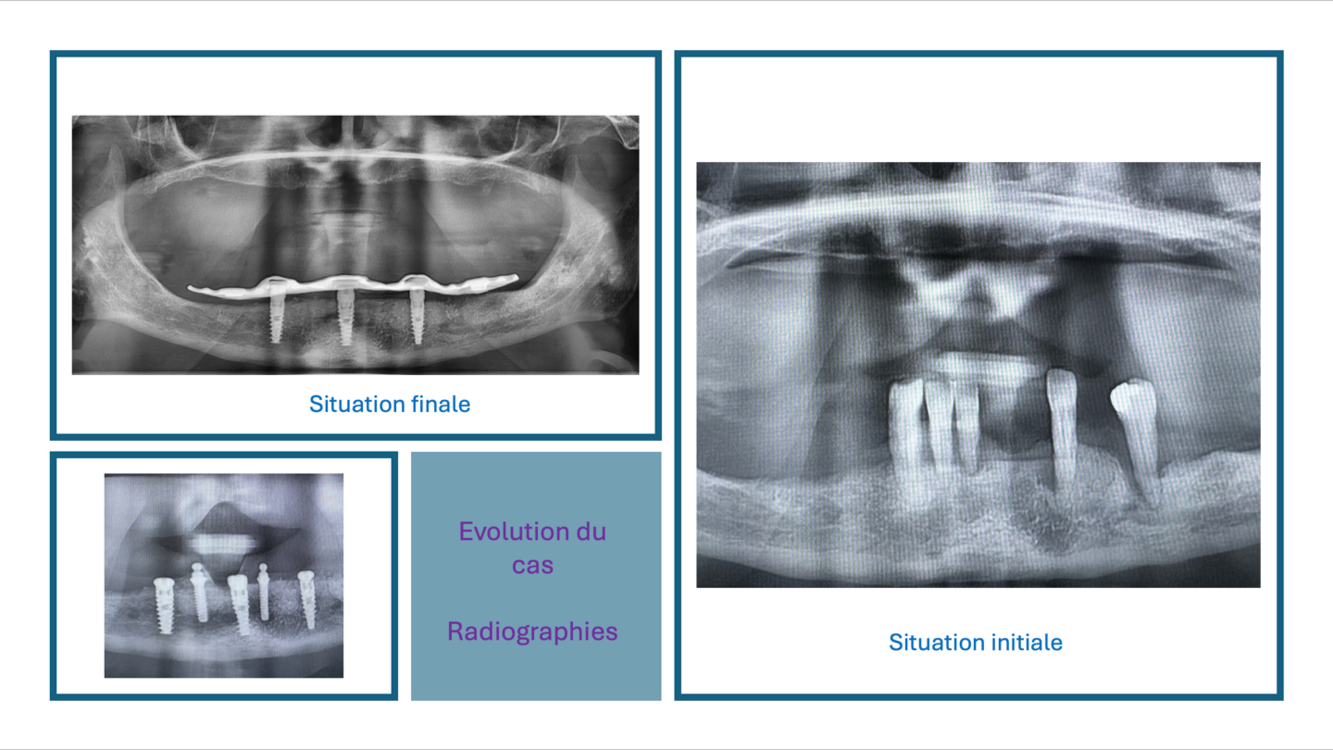

La pose de 3 implants et les extractions sont réalisées dans la même séance; une prothèse transitoire stabilisée par 2 clips transitoires est mise en place le même jour.

À 5 mois la prothèse définitive stabilisée par 3 implants est livrée à la plus grande satisfaction de notre patiente.